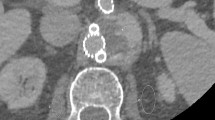

The Shapiro-Wilk test did not show normal distribution for values in all assessed groups (p < 0.05). Compared to CI, corrected attenuation in VMI at higher keV within hypo- and hyperdense artifacts significantly increased (CI/VMI200keV: −77.6 ± 81.1/−65.1 ± 103.2 HU) and decreased (47.4 ± 32.3/42.1 ± 50.2 HU), respectively (Fig. 1). However, the differences were not statistically significant. MAR significantly increased corrected attenuation in hypodense artifacts (−36.9 ± 27.7 HU, Table 1). In hyperdense artifacts, MAR decreased corrected attenuation (29.5 ± 18.9 HU), but the difference was not significant (Table 1). Combination of VMI and MAR at all keV levels significantly increased corrected attenuation in hypodense (VMIMAR200keV: −21.1 ± 26.7 HU) and decreased corrected attenuation in hyperdense artifacts (20.8 ± 25.8 HU, Fig. 1, Table 1). More detailed results on differences between reconstructions can be found in supplementary Tables 1 & 2.

Box-plot diagram displaying corrected attenuation values within hypo- and hyperdense artifacts adjacent to coiling and clipping material in conventional CT images (conventional), virtual monoenergetic images (VMI, 100–200 keV), metal artifact reduction algorithms (MAR) and their combination. Compared to conventional images, corrected attenuation within hypo- and hyperdense artifacts significantly increased and decreased, respectively, in VMI at higher keV. However, the differences were not statistically significant. MAR significantly increased corrected attenuation in hypodense artifacts. In hyperdense artifacts, MAR decreased corrected attenuation, but the difference was not significant. Combination of VMI and MAR at all keV levels significantly increased corrected attenuation in hypodense and decreased corrected attenuation in hyperdense artifacts.

Compared to CI, VMI ≥ 140 keV, MAR and combination of VMI and MAR significantly reduced hypodense artifacts (CI/VMI200keV/MAR/VMIMAR200keV, 2(1–3)/3(1–5)/3(2–4)/4 (2–5), Figs. 3–5, Table 2). Hyperdense artifacts were significantly lower in VMI at 100 keV, MAR and combination of VMI and MAR (CI/VMI200keV/MAR/VMIMAR200keV, 2(1–4)/3(1–5)/3(2–4)/4(3–5), Figs. 3–5, Table 2). Diagnostic assessment of brain tissue adjacent to coils or clips was significantly improved in VMI ≥ 100 keV, MAR and combination of VMI and MAR (VMIMAR). However, best results were generated for the combination of VMI and MAR (CI/VMI200keV/MAR/VMIMAR200keV, 2(1–3)/3(1–5)/2(1–4)/4(2–5), Table 2). Patient examples are given in Figs. 3 and 4.